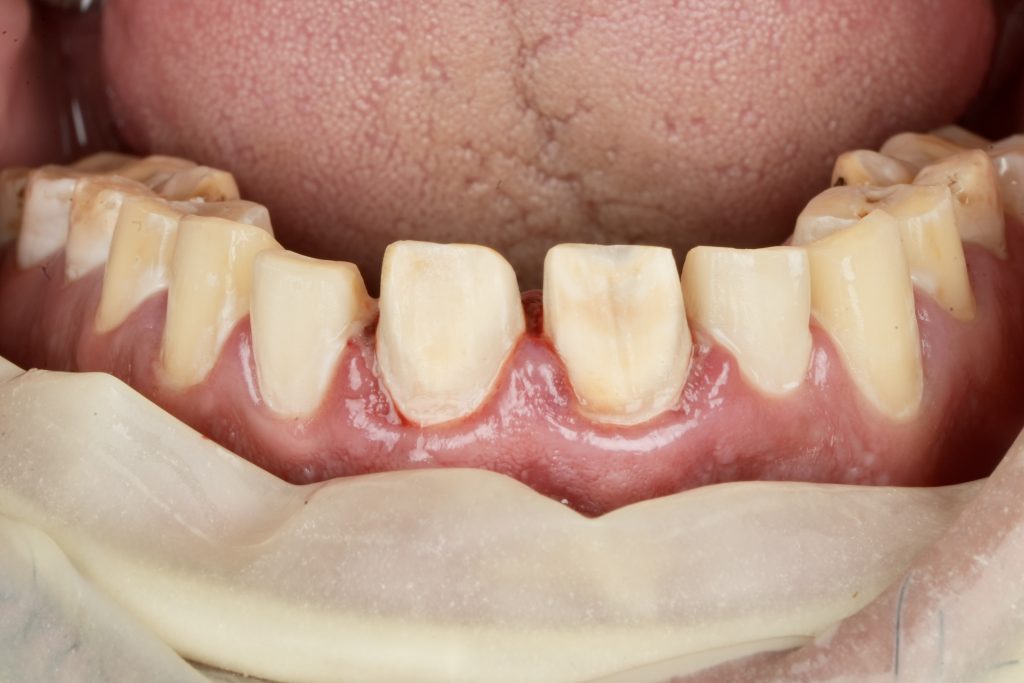

The patient sought esthetic improvement for uneven incisal edges, discolored anterior teeth, and disproportionate gingival display (Fig 1). A digital smile simulation and mock-up try-in were performed to assess tooth proportion, midline alignment, and incisal curvature. The plan prioritized enamel conservation and optical harmony.